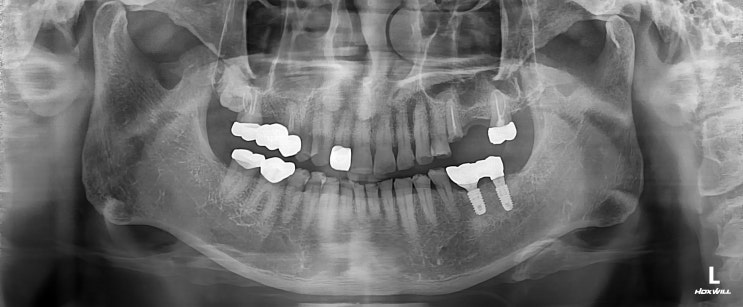

[일원동 치과] 부러진 치아 신경치료 임플란트 상악동 거상술

안녕하세요 일원동 치과 보철과 전문의 수서서울삼성치과 원장 이재현입니다 오늘은 상당히 복잡한 케이스...

[문정동 치과] 다수의 치아 상실 임플란트 치료

안녕하세요 문정동 치과 수서역 치과 수서서울삼성치과 원장 이재현입니다 이게 겨울인가 가을인가 싶은 날...